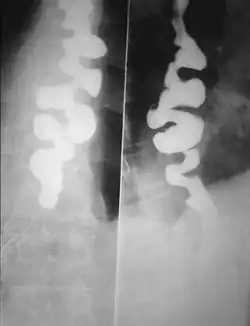

Certain abnormalities on x-ray imaging are commonly observed in DES, such as a "corkscrew esophagus" or "rosary bead esophagus", although these findings are not unique to this condition. Specialized testing called manometry can be performed to evaluate the motor function of the esophagus, which can help identify abnormal patterns of muscle contraction within the esophagus that are suggestive of DES. The treatment of DES consists primarily of medications, such as acid suppressing agents (like proton-pump inhibitors), calcium channel blockers, hyoscine butylbromide, or nitrates. In only extremely rare cases, surgery may be considered. People with DES have higher incidences of gastroesophageal reflux disease (GERD), neuromuscular diseases, and degenerative neurological disorders.

Several radiographic findings are suggestive of DES, such as a "corkscrew esophagus" or "rosary bead esophagus" appearance on barium swallow x-ray, although these findings are not unique to DES.[2]